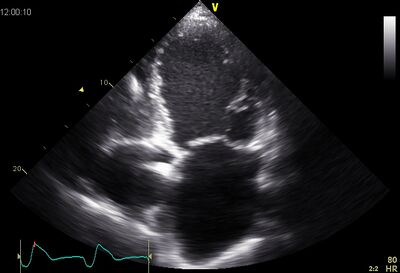

DCM01.jpg

Dilated LV on AP4CH